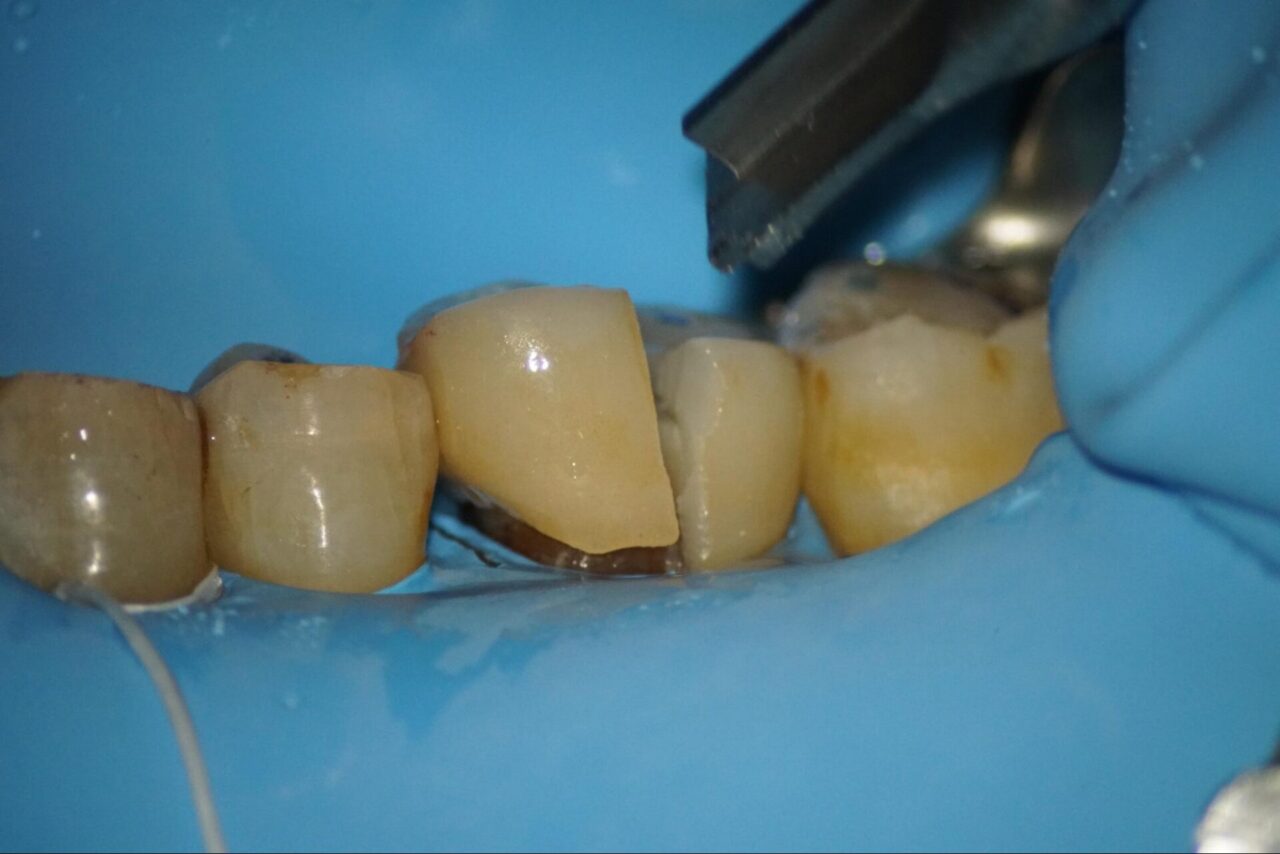

感染根管症例:実際の根管治療風景

ラバーダムをした後にクラウンを除去して、ファイバーポストの除去を行います。

レジンと歯質をきちんと分けて、除去を行なっていきます。